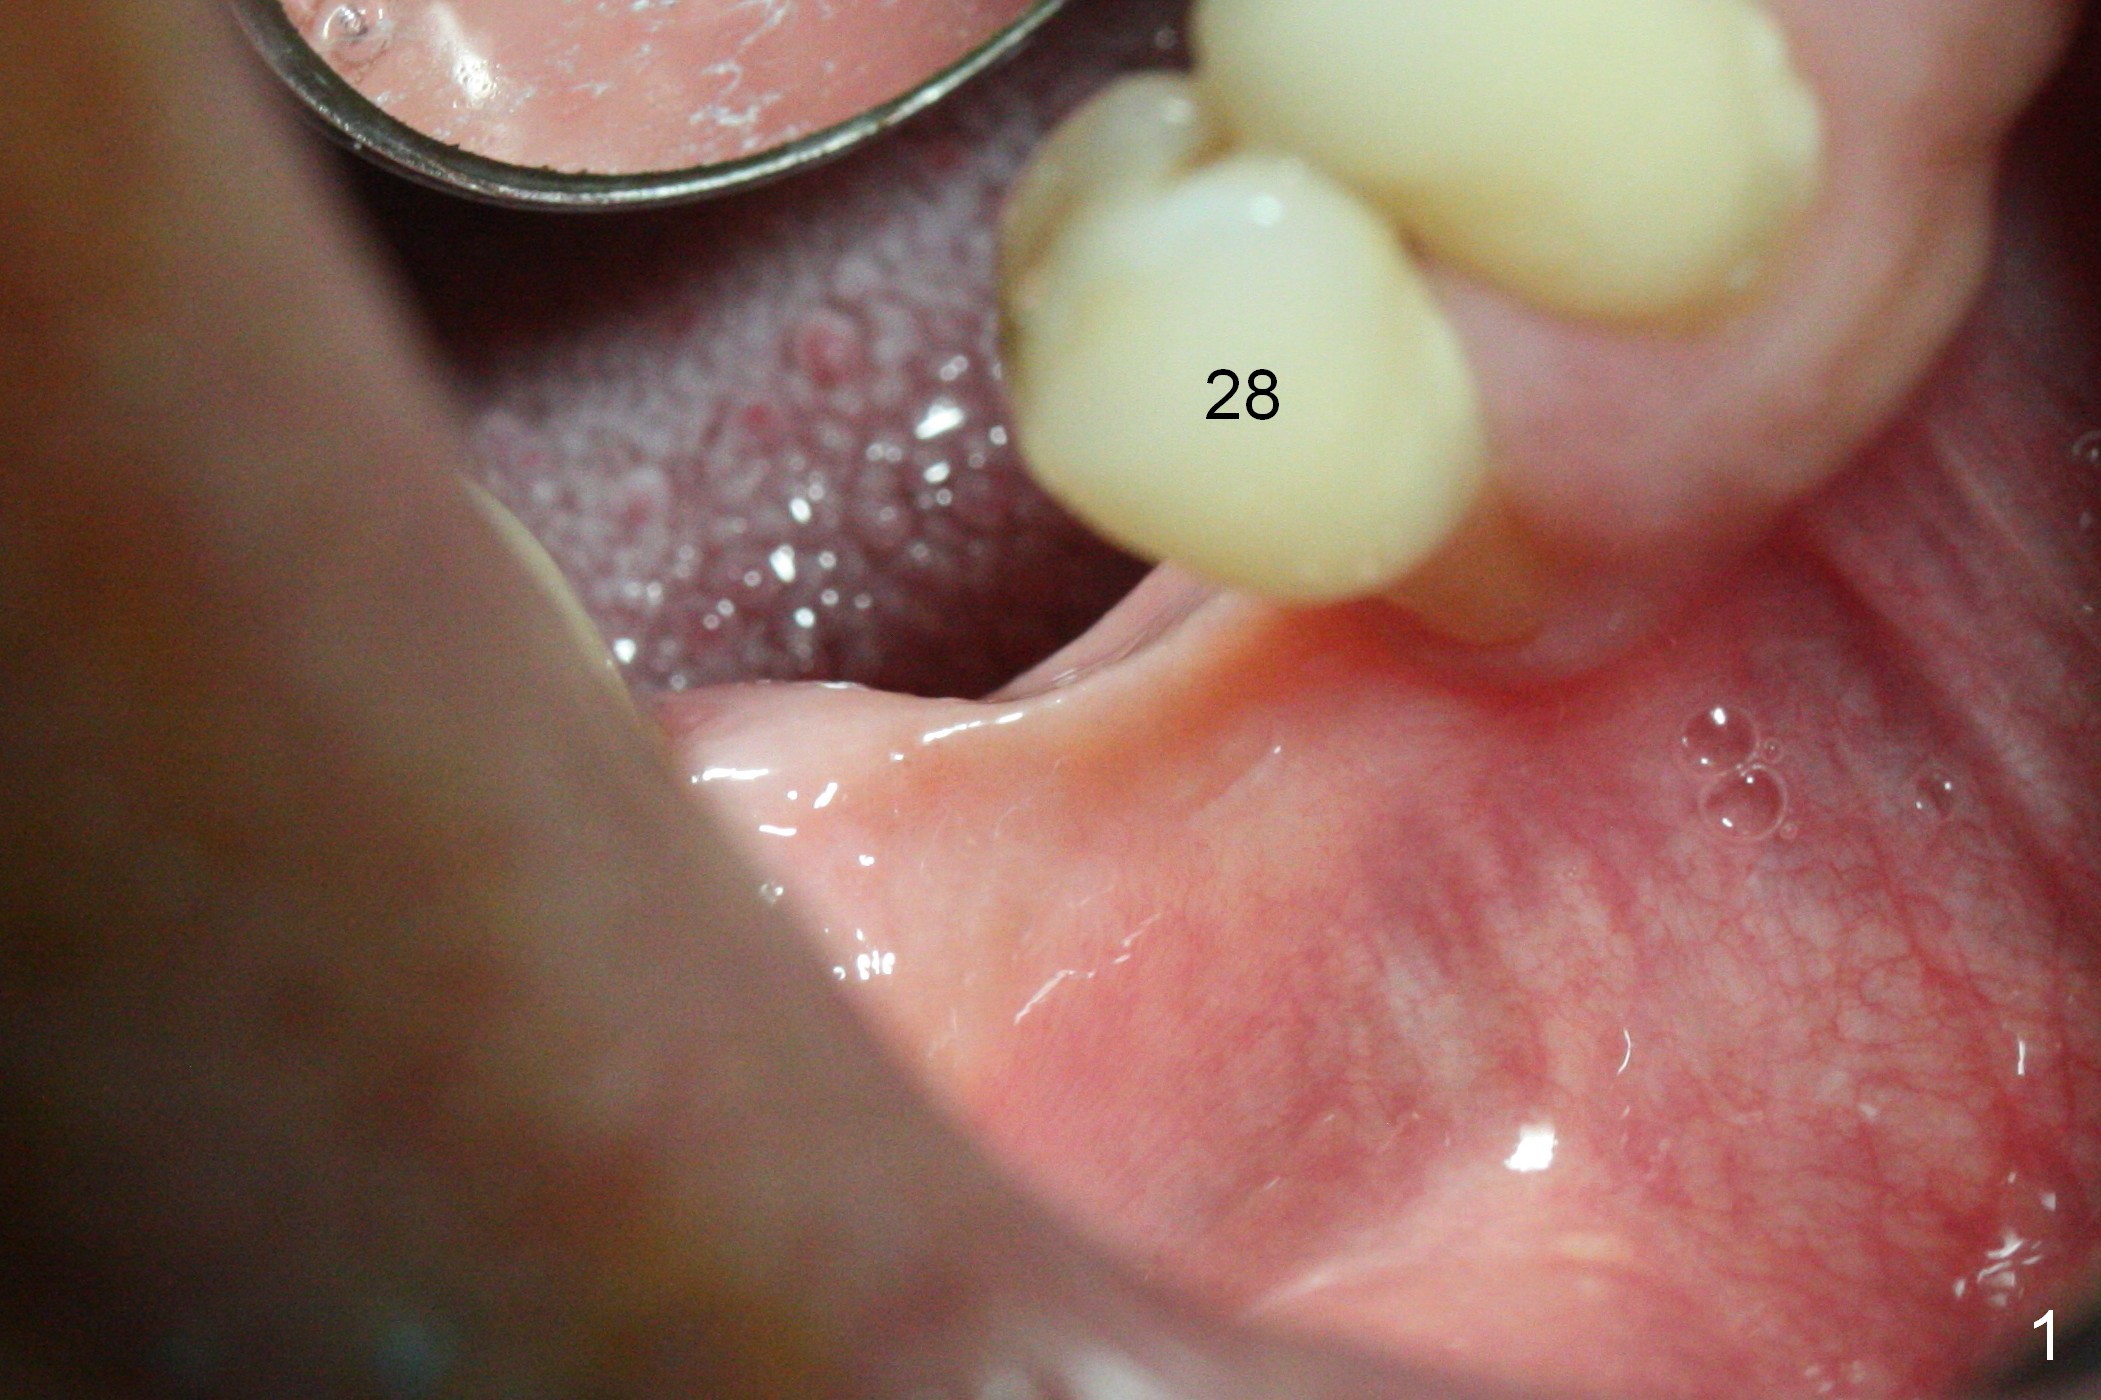

The wide mesiodistal space at #29 is most likely due to congenital missing permanent tooth (i.e., deciduous molar retention before extraction 34 years ago). The patient is now 62 years old. In fact the buccolingual width is not so narrow (Fig.1). After incision, the ridge is approximately 5 mm. Two osteotomies are established with 1.2 mm drill at 8 mm mesially and 1.5 mm one at 10 mm distally (Fig.2). The apparent approximation of the mesial osteotomy to the Mental Loop (red dashed line) is related to X-ray angulation, since there is 1-2 mm separation when two of 2x10(2) mm 1-piece implants are placed (Fig.3,4). Insertion torques of the mesial and distal implants are less than 25 and 15 Ncm, respectively. In fact bone graft is placed around the distolingual root of the tooth #30 after calculus removal (Fig.4 <). Following reduction of the abutments, periodontal dressing is applied locally. The dressing dislodged 13 days postop (Fig.5). A provisional is going to be fabricated 4 weeks postop when the wound heals (Fig.6). No bone loss is observed 4 months postop (Fig.7).